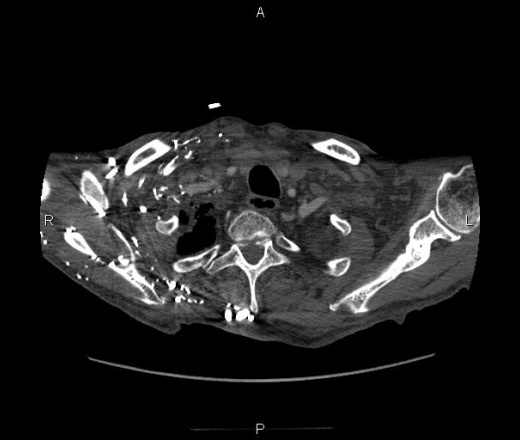

ID:50390

Ничего себе... Опухоль средостения с прорастанием ВПВ, ПГС, сердца, и мтс по плевре? Коллатерали показательные. Или первично образование сердца... саркома какая-нибудь?

да уж ! красиво, только много непонятного. Первично похоже поражено сердце , а потом распостранение по легочным сосудам и полой вене. В печени тоже какой то очаг.. Коллатерали ..как пуховый платок

Если интересно, то разбирать всё нужно по порядку. Контрастный препарат попал аж в общие подвздошные вены больше, чем в аорту.

Итак, начали исследование, выставили уровнень смартпрепа (болюс-трекинга или как угодно), после введения контрастного препарата, его не огтмечалось в аорте и лишь через 40 секунд начал появляться. Так получилось вследствие полного тромбоза верхней полой вены. Соответственно, сброса внеё из вен верхней конечности не происходило. По такой венозной сети (первый слайд) контрастный препарат попадает в НПВ и лишь после этого в камеры сердца и далее. Итак, картина достаточнот редкая, но типичная для саркомы. Локализация - праве предсердие. На гистологии - низкодифференцированная саркома.